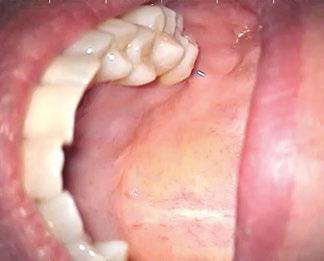

During the CVTE, I noted a small raised swelling on the palatal surface (Figure 6) and a separate white nodular lesion on the buccal gingiva adjacent to tooth No. 14 (Figure 7). Importantly, these findings did not align with any odontogenic pathology typically associated with tooth No. 14. That clinical inconsistency provided the moment to pause and widen the diagnostic lens.

This patient was compliant and presented to the OMS the next day. The OMS performed their own examination and determined that a biopsy was necessary. The biopsy results revealed:

“Diffuse large B-cell lymphoma of the left maxillary sinus, germinal center phenotype” (Figure 8).

Figure 6 (left): Palatal swelling. Figure 7 (right): Buccal nodular lesion